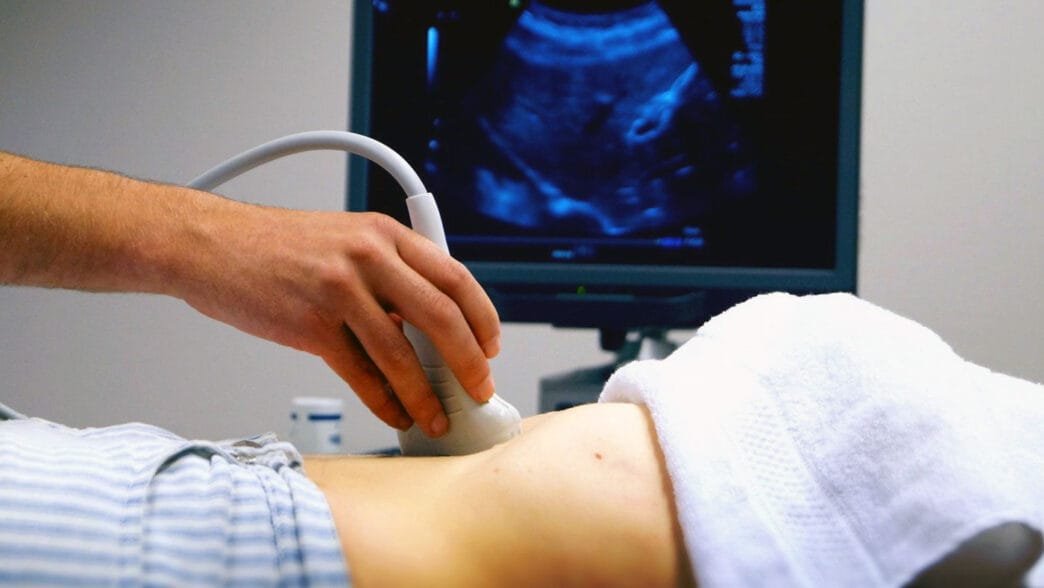

Ayrıntılı Ultrason Nedir ve Nasıl Uygulanır?

“Ayrıntılı ultrason” ya da diğer adıyla “detaylı ultrasonografi”, anne karnında büyüyen bebeğin organlarının oluşumunu ve gelişimini inceleyen bir görüntüleme yöntemidir. Bu yöntem, özellikle bebeğin beyin, kalp, akciğer, böbrek gibi önemli organlarının gelişimini takip etmeyi amaçlar. Ayrıntılı ultrasonografi ile bu organların büyüme sürecinde bir sorun olup olmadığı belirlenebilir. Bebeğin beyni, gözleri, burnu, dudakları, kalbi, kolları, bacakları gibi birçok bölgesi ayrıntılı olarak değerlendirilir ve doğum öncesi olası yapısal anomali riskleri incelenir.

Anne karnındaki bebeğin gelişimi iki ana döneme ayrılır: embriyolojik dönem ve fetal dönem. İlk 8 hafta embriyolojik dönem olarak adlandırılır ve bu süreçte bebeğin temel yapıları oluşmaya başlar. Bu dönemden sonra gelen fetal dönem ise 8. haftadan doğuma kadar devam eder ve bu süreçte bebeğin tüm organları hızla gelişmeye devam eder. Ayrıntılı ultrasonografi genellikle fetal dönemin 18-24. haftaları arasında uygulanır. Bu dönemde bebeğin organları büyük ölçüde oluşmuş olduğundan, detaylı bir inceleme yapmak mümkündür. Ancak, gelişen teknoloji sayesinde bu inceleme artık 11-13. haftalar arasında da yapılabilmekte ve böylece erken teşhis şansı artmaktadır. Yine de bazı yapısal bozukluklar bu haftalarda görülemeyebilir, bu nedenle özellikle beyin ve kalp ile ilgili detaylı değerlendirmeler için 20-24. haftalarda tekrar ultrason önerilir.

Ayrıntılı ultrasonografi, kullanılan yüksek frekanslı ses dalgalarıyla bebeğin detaylı görüntülerini elde eder. Bu işlem, tamamen güvenlidir ve hem anneye hem de bebeğe herhangi bir zarar vermez. Ultrason süresinin uzun olması nedeniyle bazı anne adayları bebeklerinin bu işlemden olumsuz etkilenebileceği kaygısını taşıyabilirler. Ancak bilimsel çalışmalar, bu cihazların bebeğe hiçbir zararı olmadığını ve güvenle kullanılabileceğini göstermiştir. Ultrason sırasında kullanılan ses dalgaları, vücutta radyasyon gibi zararlı etkiler yaratmaz; dolayısıyla bu işlem tamamen güvenlidir.